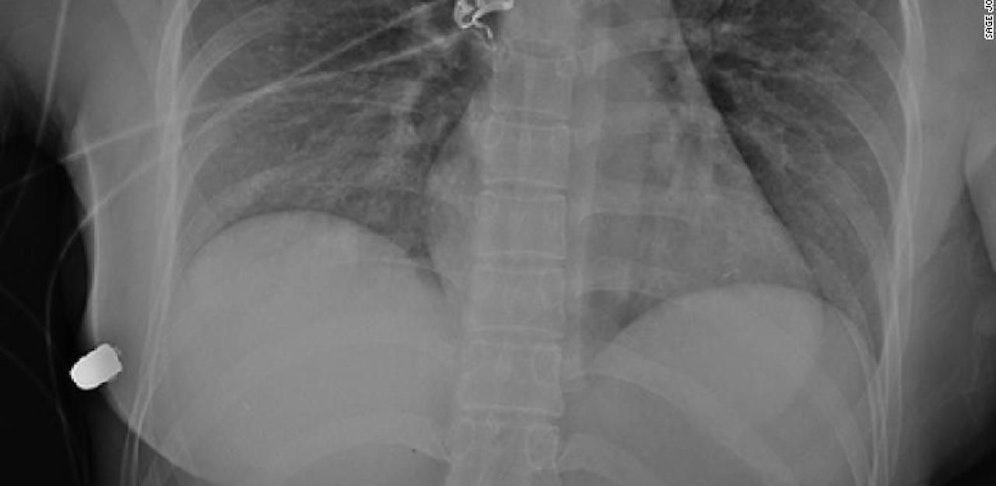

Eine 30-jährige Frau aus Kanada überlebte einen Schuss, der aus nächster Nähe auf sie abgefeuert worden war – wegen ihres Silikon-Brustimplantates. Dieses lenkte die Kugel ab und schützte so die lebenswichtigen Organe.

Die Frau habe riesiges Glück gehabt, dass das Implantat die Flugbahn der Kugel in der Brust abgelenkt habe. So kam sie statt mit lebensgefährlichen inneren Verletzungen mit gebrochenen Rippen und einem zerplatzten Implantat davon.